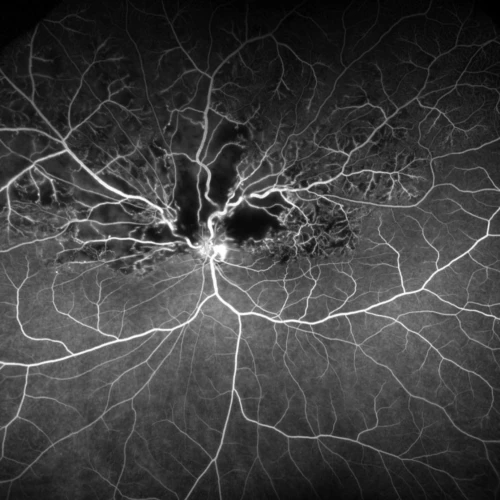

We are proud to announce our new fundus fluorescein angiogram available at our clinic. This allows us to provide full scope care for medical retina patients, including the treatment of AMD, diabetic retinopathy, and retinal vascular occlusions. Optos produces ultra wide-field images with a field of view up to 200 degrees, compared to standard angiogram images of around 70 degrees. This enlarged field of view influences the management of conditions that affect the peripheral retina, in particular diabetic retinopathy and vascular occlusions.